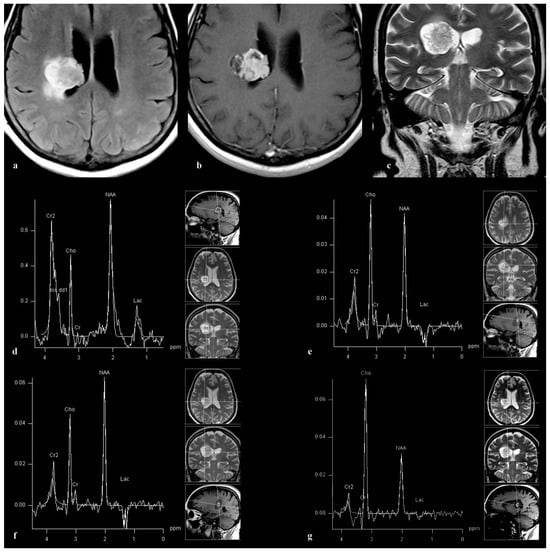

3.1. Patient 1